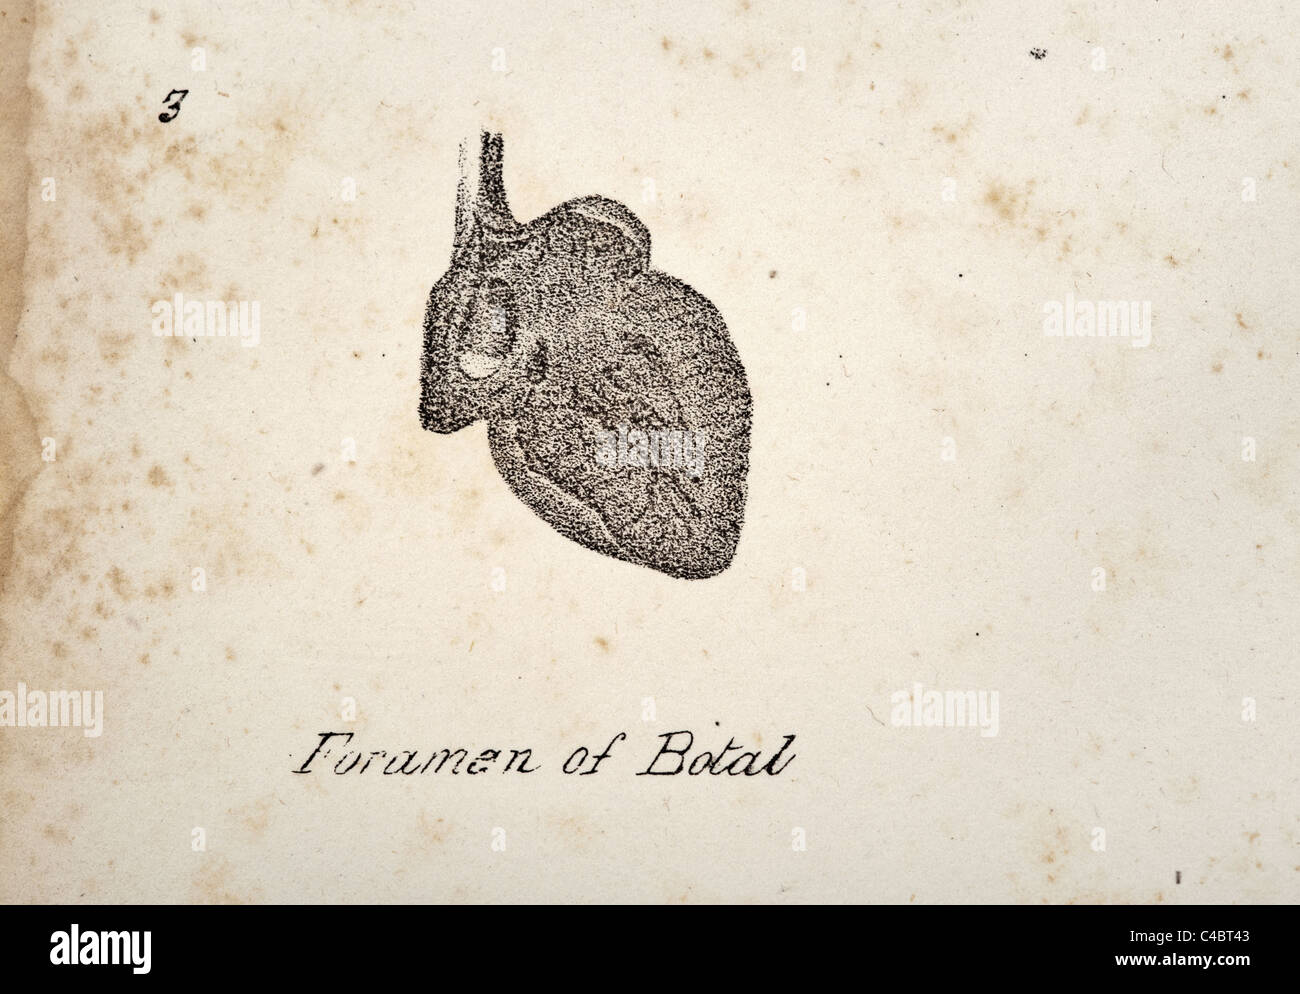

- Fetal Hi-Res Stock Photography And Images - Alamy

Find More About "Fetal Movements Hi Res Stock Photography And Images Alamy"